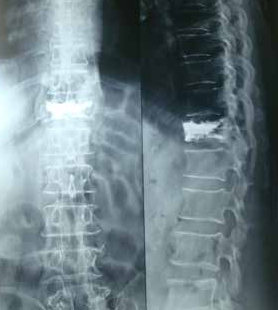

Surgical Treatments of Vertebral Fractures: depends upon the fact that there is only fracture or fracture associated with spinal cord compression. If there is only fracture then cement filling procedure (Vertebroplasty ) is a miraculous procedure under local anesthesia where the patient walks immediately following the surgery. If there is compression of spinal cord leading to weakness in legs then open surgical stabilization with screws is contemplated. Never the less the medical treatment is always to be continued for long. Spinal fixation Vertebroplasy

Multilevel fixation with cement vertebroplasty for osteoporetic fracture non uniting

Percutanious V plasty Percutaneous cement vertebroplasty under local anesthesia. Patient usually walks in 2hrs.